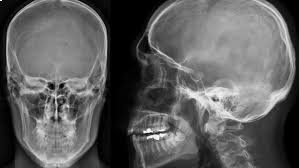

La radiologia convenzionale è l’esame di primo livello per lo studio di molteplici distretti corporei e in particolare dell'apparato respiratorio e scheletrico (cranio, colonna vertebrale, segmenti ossei). Questa metodologia fornisce importanti indicazioni di base su molte patologie, sia traumatiche che degenerative e artrosiche nonché malformative. La radiologia convenzionale si risulta anche di grande efficacia per individuare patologie o problematiche all'apparato urinario e all'addome, da approfondire successivamente con esami diagnostici più accurati e precisi.